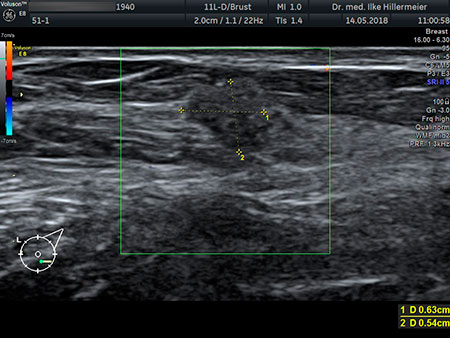

Frauenarztpraxis Dr Ilke Hillermeier